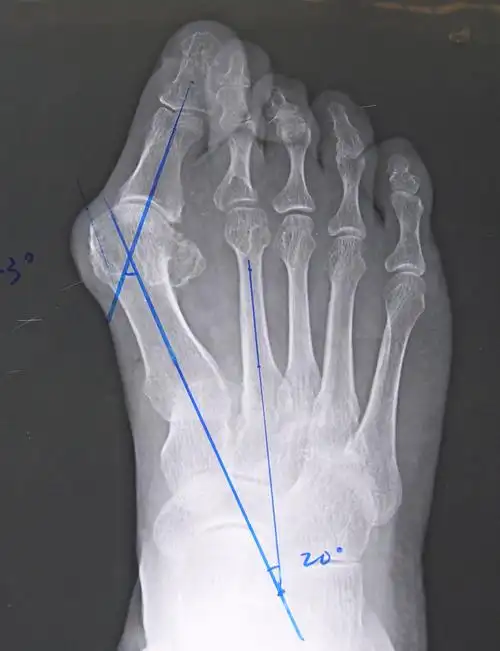

大脚骨scarf akin截骨 - 好大夫在线

如果大脚骨手术不是削掉骨头那么到底应该怎么做才好呢